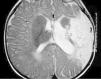

Ante los hallazgos clínicos, a los 3 días de vida se realiza resonancia magnética (RM) cerebral, apreciándose un extenso infarto agudo dependiente de la arteria cerebral media derecha (fig. 1). El EEG y la ecografía cerebral realizadas a los 5 días, mostraron, respectivamente, presencia de ondas agudas frontales derechas ocasionales y un aumento de ecogenicidad en la región parietal, temporal derecha y tálamo derecho. Se completó el estudio con una ecografía Doppler cerebral y una angio-RM (fig. 2) que objetivaron ausencia de flujo en arteria cerebral media derecha confirmando el diagnóstico de infarto cerebral.

Figura 2. Angio-RM: ausencia de ACM derecha.